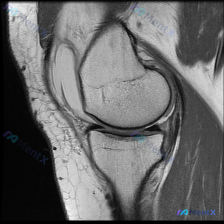

怀疑踝关节软骨异常?这张T1MRI居然没发现异常,问题出在哪?

本次读片对象是踝关节MRI T1加权矢状位图像,核心疑问是:图像中是否存在软骨异常?

- 影像质量:图像清晰,解剖层次分明,对比度良好,无明显伪影,可清晰分辨骨髓、骨皮质和软组织

- 解剖结构显示范围:完整覆盖胫骨远端、距骨、跟骨、足舟骨、骰骨、楔骨及跖骨基底部,足底软组织也清晰可见

- 骨骼系统评估:所有骨骼骨髓信号均匀,无局灶低信号;骨皮质连续光滑,无骨折、骨质破坏或明显骨赘增生

- 关节与软骨评估:所有可见关节间隙清晰对称,关节软骨表面平整,厚度均匀,未见剥脱、缺损或信号异常;各关节对位良好,无脱位半脱位

- 软组织评估:跟腱、足底筋膜等肌腱筋膜结构完整,信号均匀;关节囊无膨隆,滑膜无增厚,无明显异常关节积液;皮下软组织无异常水肿或占位

读片初步结论:该层面T1加权图像未见明确异常,也没有观察到支持软骨异常的征象。